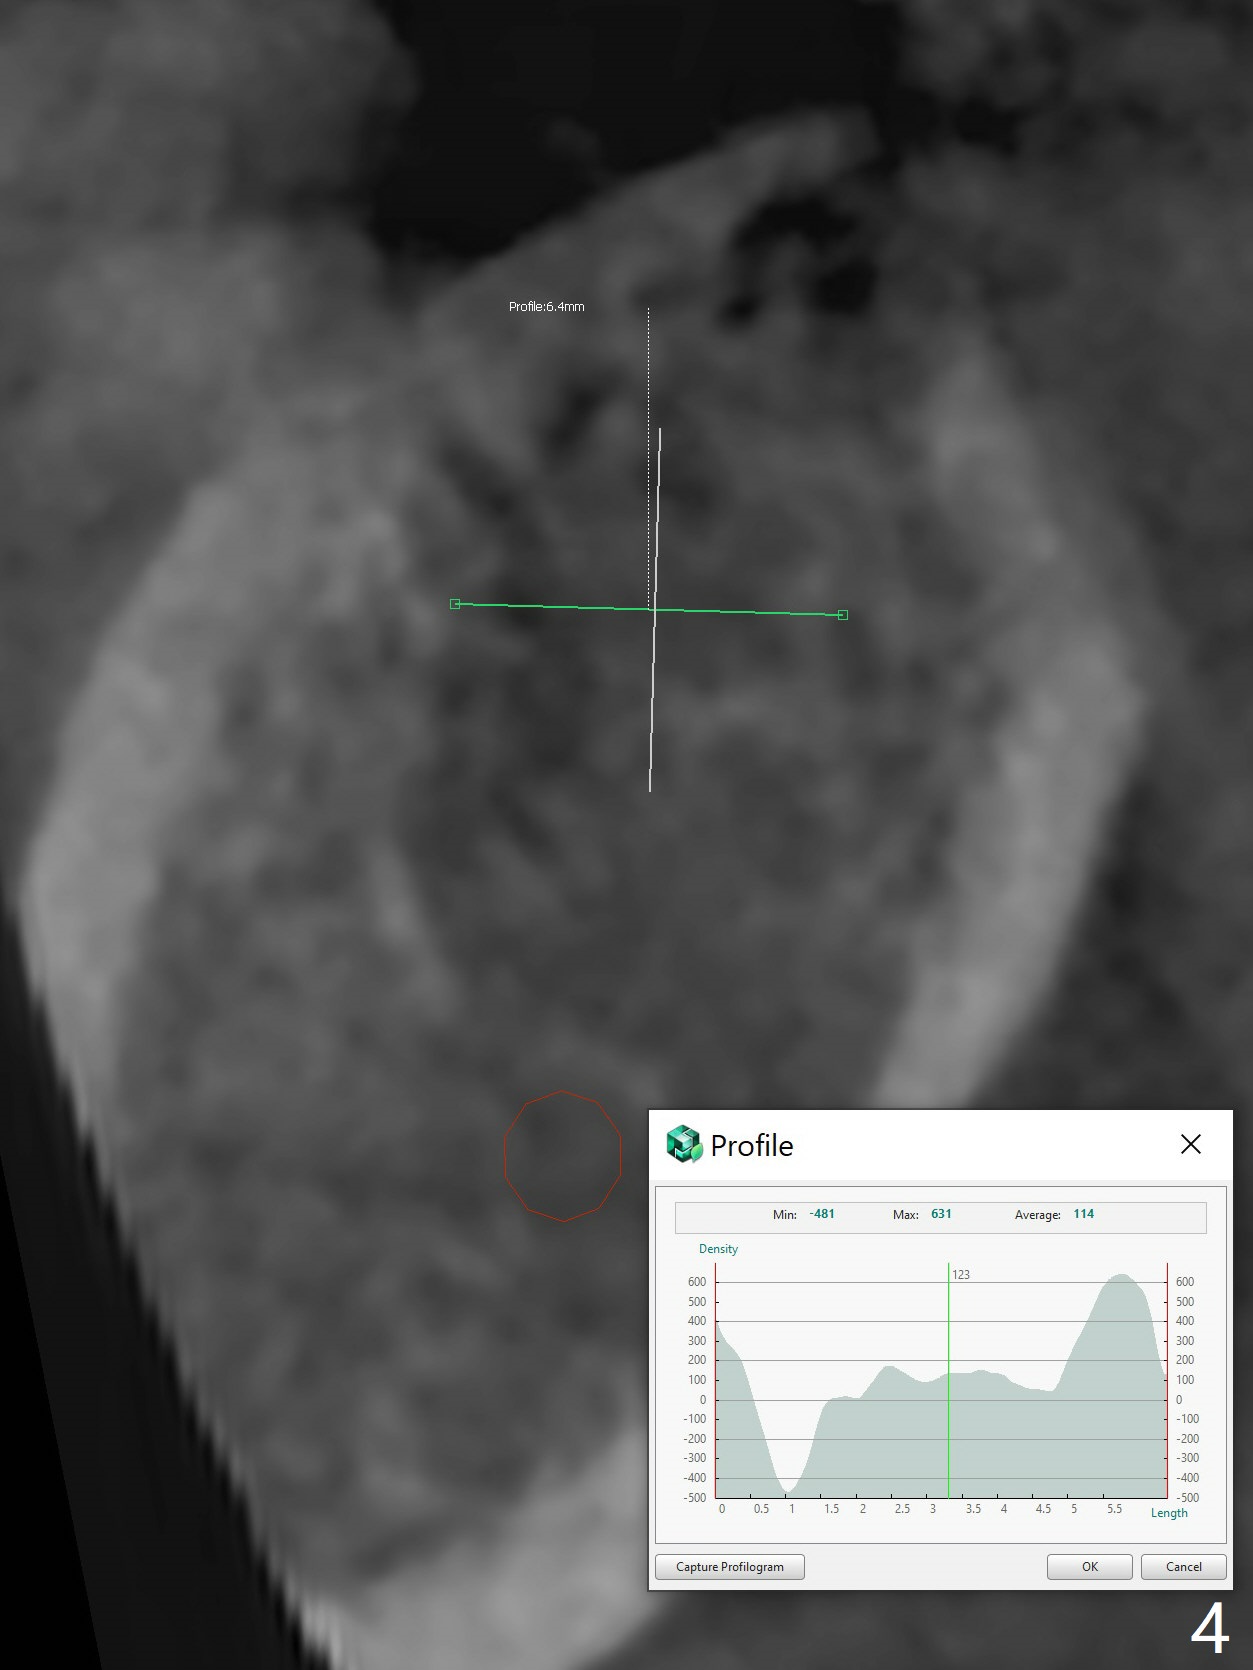

61岁女同意先做右下7植牙,可能困难是对合牙过度萌出(图一:箭头),还好对合牙牙尖比较长,有余地磨除。虽然牙槽骨很宽(图二),但是牙槽嵴顶(图三:>)缺乏皮质骨,密度很低(图四)。所以钻头必须小(4毫米),不必攻螺纹。